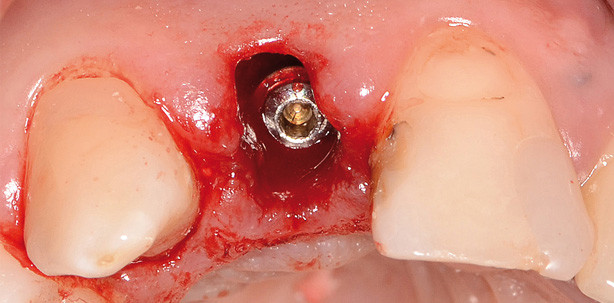

Beim chirurgischen Vorgehen muss der oft angeführten Doktrin widersprochen werden, dass eine knöcherne Blockaugmentation immer zwingend erforderlich ist. Korrekt ist, dass eine Augmentation in geeigneter Form, meist partikulär, praktisch immer nötig ist. Korrekt ist, dass bei einer Sofortimplantation ohne lappenbildende Schnitte der Erhalt der ursprünglichen Weichgewebssituation erreicht werden kann. Es ist auch korrekt, dass für einen Erfolg das korrekte chirurgische Vorgehen und die Wahl eines geeigneten Implantatsystems essenziell sind. Im Umkehrschluss muss bemerkt werden, dass gegebenenfalls nicht alle Implantate für diese kritische Indikation sinnvoll sind. Entscheidende Erfolgsfaktoren beim chirurgischen Vorgehen sind:

• Eine schonende Extraktion des vorhandenen Zahnes ohne Schnittführungen.

• Die korrekte Positionierung des Implantates hinter den knöchernen Envelope. Dies ist im Wesentlichen eine manuelle Behandlungsaufgabe des Chirurgen. Es muss der Annahme widersprochen werden, dass jede Art von Bohrschablone hier die chirurgische Erfahrung und Taktilität ersetzen kann.

• Eine korrekte Deckung der Situation. Sollte ein Patient mit einem herausnehmbaren Provisorium zufrieden sein, kann alternativ zur Sofortkrone eine kostengünstigere Deckung mit einem speicheldicht abschließenden Gingivaformer oder eine Weichgewebsdeckung mittels freiem Bindegewebs- oder Schleimhauttransplantat bzw. getunneltem Lappen erreicht werden. Das freie Bindegewebstransplantat mag im frisch operierten Zustand sehr unästhetisch wirken, verheilt aber, wie alle korrekt gesetzten Wunden im Gaumen und Attached Gingiva-Bereich narbenfrei und mit perfekter ästhetik (Abb. 2). Im Maximalversorgungskonzept kann die Deckung durch eine Sofortversorgung mit speicheldichtem Abschluss des Aufbaues erfolgen, wie von Noelken et al. dargestellt. Man muss hierzu bemerken, dass der Aufwand für dieses Vorgehen nicht für jeden zuweisenden Kollegen oder chirurgischen Primärbehandler praktikabel ist. Die Sofortversorgung mit einem individuellen Kompositaufbau, entweder laborgefertigt oder chairside erstellt, erfordert einen hohen Kostenaufwand, der nicht von jedem Patienten getragen wird. Die Kosten liegen bei sinnvollem Deckungsbeitrag und abhängig vom Implantatsystem fast im Bereich der späteren Dauerversorgung. Die Wahl der geeigneten Technik ist abhängig vom Patienten, der Situation und der Gesamtplanung individuell zu treffen:

• Die Anatomie der drei verschiedenen Formen von Alveolen und Zahnsaumkonfigurationen ist bei der Deckung bei der Sofortimplantation zu berücksichtigen (Abb. 3).

• Im Bereich der 1er ist es aufgrund der runden/rund-dreieckigen Anatomie des Weichgewebes meist möglich, mit üblichen Gingivaformern einen sinnvollen Verschluss zu erreichen, was im Bereich der 2er und 3er von Fall zu Fall geprüft werden muss (Abb. 3–5).